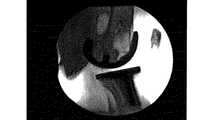

図1を参照すると、正常な膝関節はACL及びPCLを含む。正常な関節の場合、ACLの動作は大腿骨を前方に引くように作用し、膝関節は全伸展位に向けて移動する。反対に、PCLの動作は大腿骨を後方に引くように作用し、膝関節は全屈曲位に向けて移動する。図1が示すように、正常な膝関節がほぼ全伸展位であると、大腿骨が脛骨の前面に接触し、膝蓋骨が大腿骨と接触することが分かる。これは、PCR TKAにおける大腿骨と膝蓋骨の位置とまさに対照的である。 Referring to FIG. 1, a normal knee joint includes ACL and PCL. In the case of a normal joint, the movement of the ACL acts to pull the femur forward, and the knee joint moves toward the fully extended position. On the other hand, the movement of the PCL acts to pull the femur backward, and the knee joint moves toward the total bending position. As shown in FIG. 1, when the normal knee joint is in the fully extended position, it can be seen that the femur contacts the front surface of the tibia and the patella contacts the femur. This is in stark contrast to the femur and patella positions in PCR TKA.

図2を参照すると、PCR TKAは、本来ならACLに帰属する反作用力を伴わずに、そこなわれていない状態でPCLを保持し、屈曲と共にPCLが大腿骨を後方に引くことを可能にする。PS TKAにおいては、膝の屈曲の増加と共にカム/支柱機構の力が大腿骨を後方に押しやるが、今日の全膝関節移植術では、屈曲位から全伸展位にかけて前方安定は存在しない。全伸展位では、正常な膝に比べ、PS及びPCR TKAの両方で大腿顆は脛骨インサートに後方により多く接触するので、大腿骨構成要素からの膝蓋骨構成要素の分離をもたらし、活動中、大腿骨構成要素は運動全体にわたり後方に維持される。 Referring to FIG. 2, PCR TKA holds the PCL unbroken, without the reaction force originally attributed to the ACL, and allows the PCL to pull the femur back with flexion. . In PS TKA, as the knee flexion increases, the force of the cam / post mechanism pushes the femur backward, but in today's total knee arthroplasty there is no anterior stability from flexion to full extension. In the fully extended position, the femoral condyle more posteriorly contacts the tibial insert in both PS and PCR TKA compared to a normal knee, resulting in separation of the patella component from the femoral component, The component is maintained backward throughout the movement.